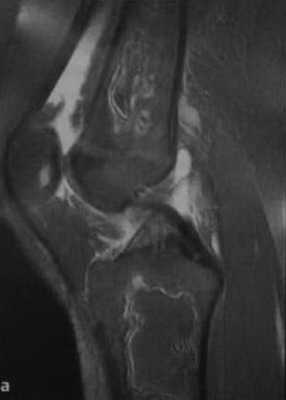

а, b Инфаркт зрелого костного мозга. (а) Сагиттальная протонная плотно-взвешенная МРТ с подавлением МР-сигнала от жировой ткани. Изображение демонстрирует гирляндовидный склеротический край и центральный участок с сигналом жирового костного мозга. Множественные некротические зоны расположены преимущественно в метадиафизальной области, однако несколько находятся непосредственно рядом с суставом, в связи с чем имеется риск уплощения суставных поверхностей;

b) Рентгенологическое исследование демонстрирует выраженный склеротический край и центральный участок снижения рентгенопрозрачности в дистальном отделе бедренной кости и в большеберцовой кости. Проксимальный отдел бедренной кости демонстрирует участок частичного грубого склероза, который иногда трудно отличить от энхондромы.